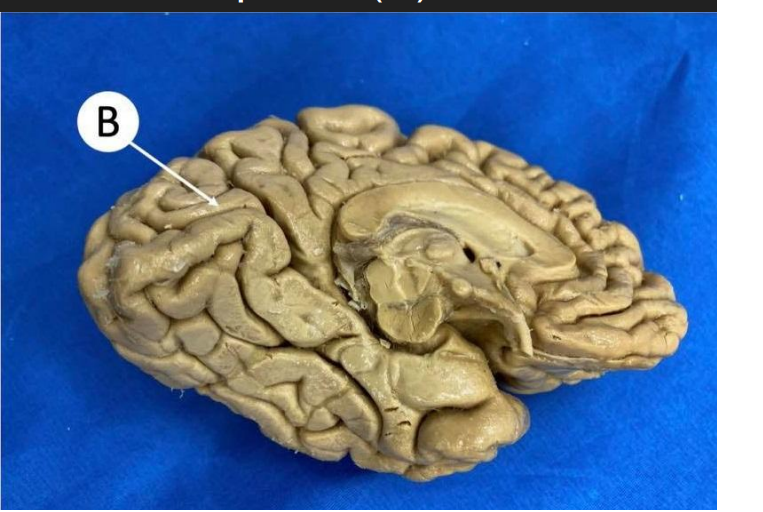

corpus callosum

Aquaeductus mesencephali

Thalamus Dex.

capsula interna sin.

ventriculus lateralis dex.

Insula Dex.

ventriculus III

komora III